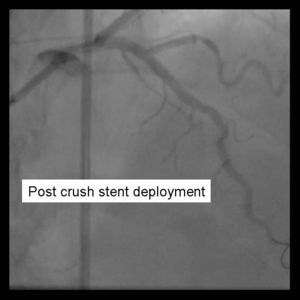

11) Kissing balloons are inflated at the bifurcation. It is sometimes necessary to dilate the sidebranch with a small balloon (1.5 mm middle marker balloon) to facilitate a larger balloon for the kiss.

12) Repeat angiography is performed. Wires are removed and final angiography completed.

Despite excellent initial angiographic results, side branch restenosis is still a significant problem with Crush stenting(Up to 25% without kissing ballon inflation). However,most of the restenosis is silent. The above example used Cypher drug eluting stents in the Side branch and Parent vessels. The patient returned with positive stress testing 13 months later. Repeat angiography demonstrated a short segment of significant in-stent restenosis.